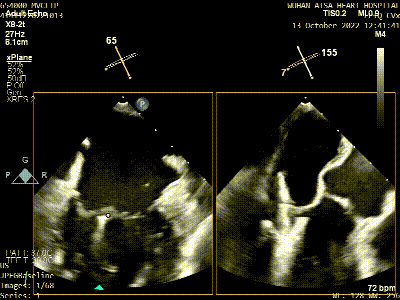

患者全身麻醉消毒铺巾后,建立右侧股静脉入路,在经食道超声指导下房间隔穿刺。根据要求,房间隔穿刺高度至少需要4.0cm,患者本身的解剖结构,左房和右房都比较小,如果选取卵圆窝靠后,靠中上的位置穿刺点高度只有2.6cm,是无法完成整个手术操作的,那么想要在安全的前提下获得更充分的房间隔穿刺高度,考虑选择在房间隔肌部穿刺,采用穿刺针的内芯,PCI导丝,甚至电刀穿刺的方式,都无法突破房间隔。患者的卵圆窝松弛,肌部又硬,苏晞院长团队决定在肌部与膜部交界的位置穿刺,经过精细调整,精准定位,最终以3.64cm的极限高度突破房间隔,而后将MitraClip™可操控导引导管(SGC)送入左心房。

将MitraClip™XTR送入左房,由于左房太小,在达到骑跨过程中反复推进回撤CDS和稳定器,同时旋转SGC,达到骑跨的同时,保证Clip头端游离,且SGC在左房有深度。旋转M,同时顺时针往后旋转SGC借高度,使Clip垂直二尖瓣环平面,由于穿刺高度不够,Clip直接进入左室,这意味着操作要十分小心,左室组织复杂,稍有不慎将会造成组织损伤。使用A/P Konb中“A”旋钮借高度。确认垂直后,直接在左室打开Clip,3D外科视角,逆时针旋转使Clip夹臂处于11点-5点方向,回拉稳定器,使Clip处于3区脱垂区域,用“+/-”Knob中的“-”旋钮,使Clip更往后叶的同时增加操作高度,抓捕脱垂的瓣叶,关紧Clip后,反流从4+降低至0级,平均跨瓣压差2mmHg,左右肺静脉逆流均改善。前后叶活动度降低,后叶插入长度9mm,前叶插入12mm, 确认稳定性后释放Clip。释放后,即刻效果十分满意,手术圆满结束。